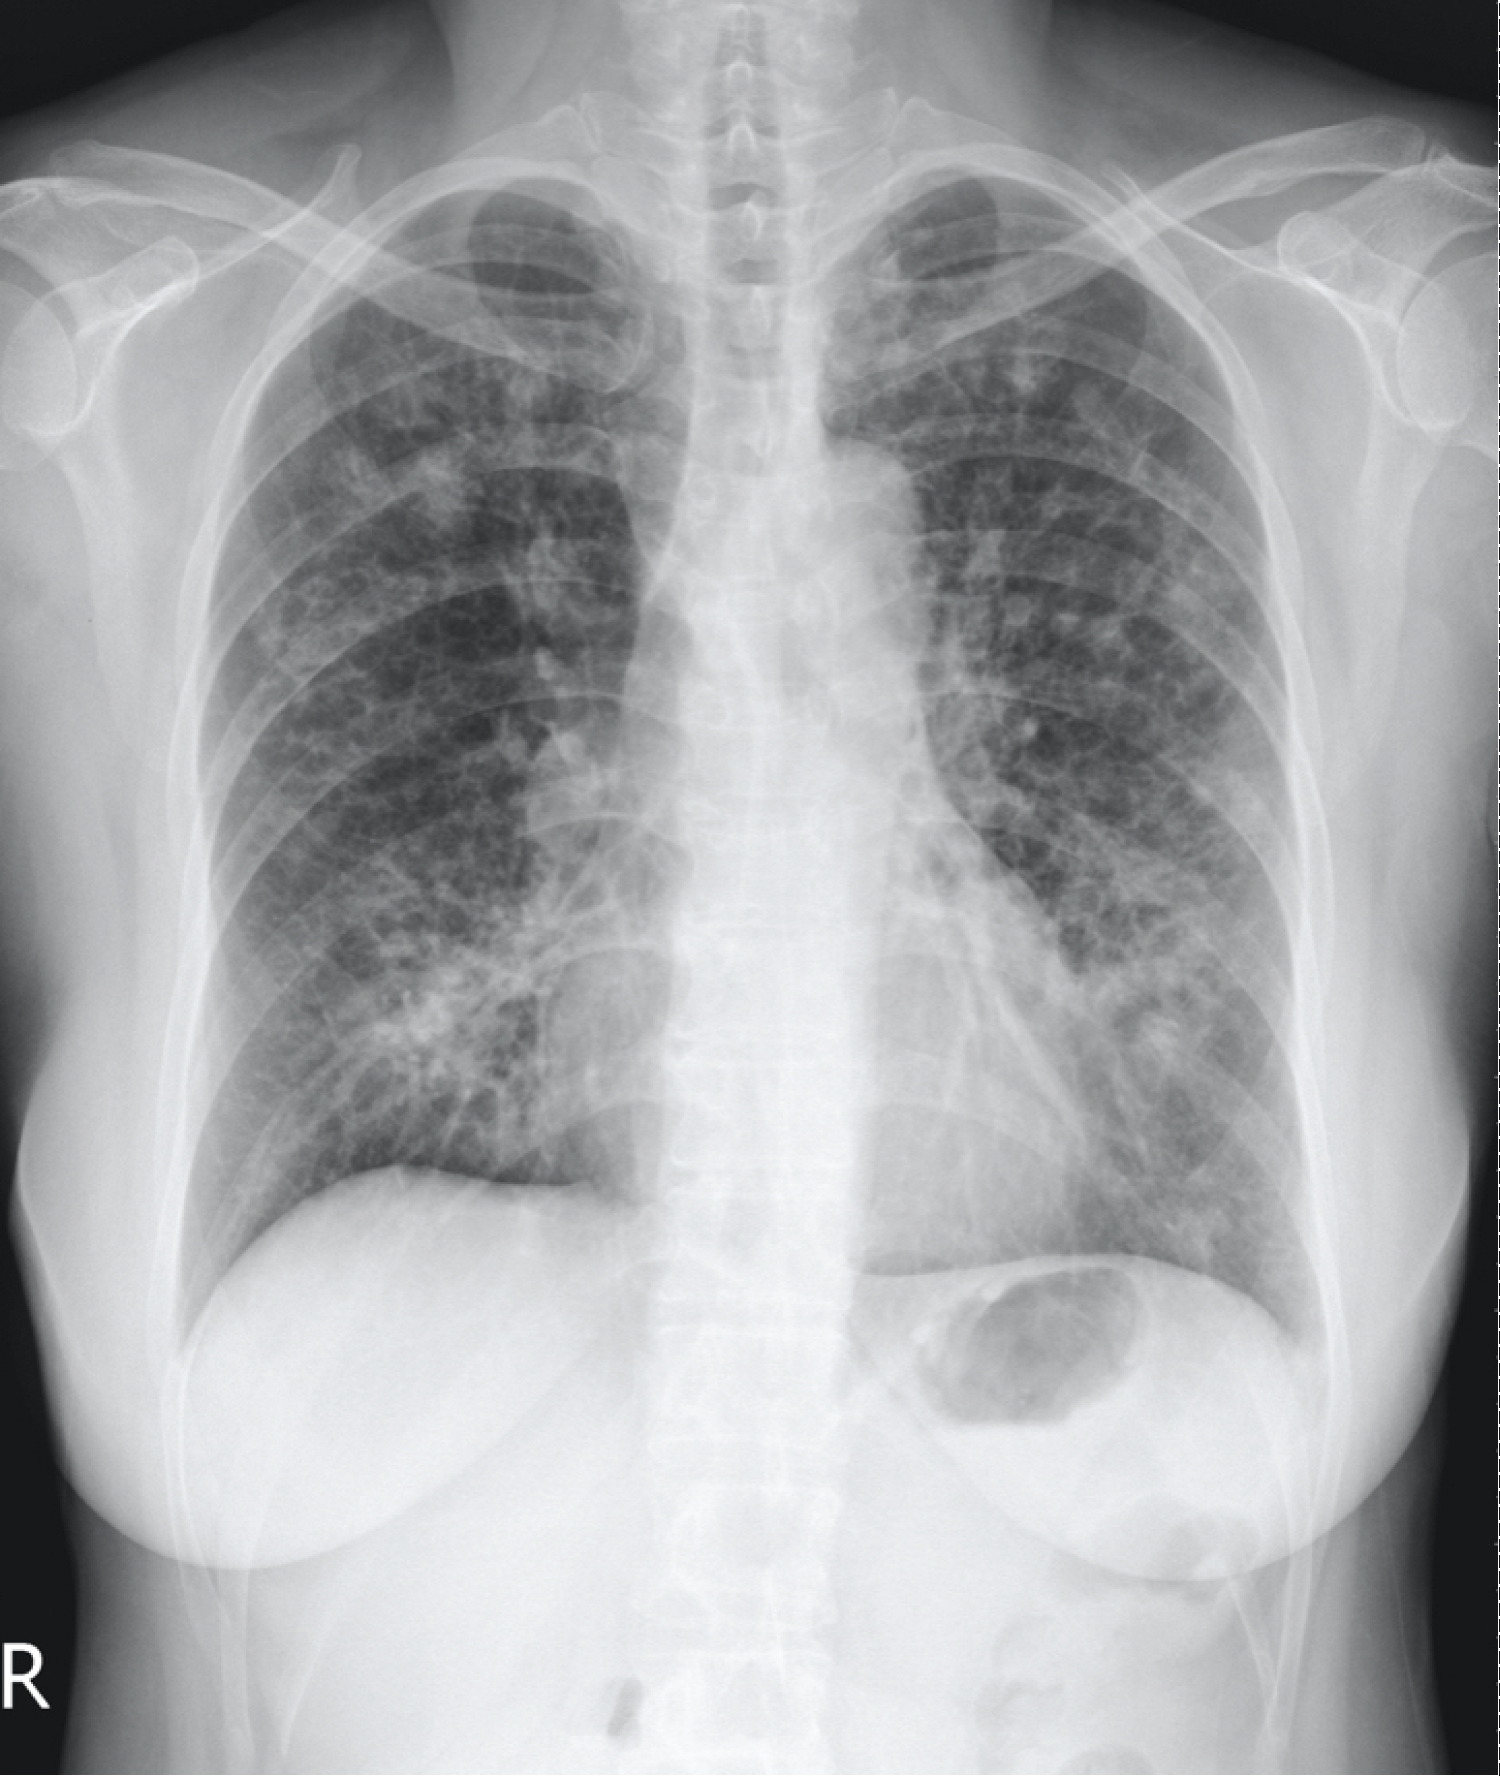

A 60-year-old non-smoking, slender woman without significant medial history presented with a 6-month history of intermittent low-grade fever, dyspnea, and productive cough with greenish sputum. Physical examination revealed crackles in both lung fields. Laboratory tests showed a white cell count of 21,700/μL (reference range 3,200 to 9,200). Chest radiography revealed multiple linear, nodular opacities, and infiltrates inboth lung fields (Figure 1). Computed tomography illustrated nodular bronchiectasis in the right middle lobe (RML) and the left lingua (Figure 2).

Figure 1: Chest radiography revealed multiple linear, nodular opacities, and infiltrates in both lung fields.